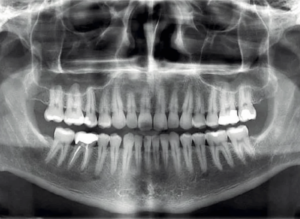

Ortopantomografía

La ortopantomografía es una herramienta útil para el diagnóstico en odontología, cirugía bucal, implantología, ortodoncia o periodoncia.